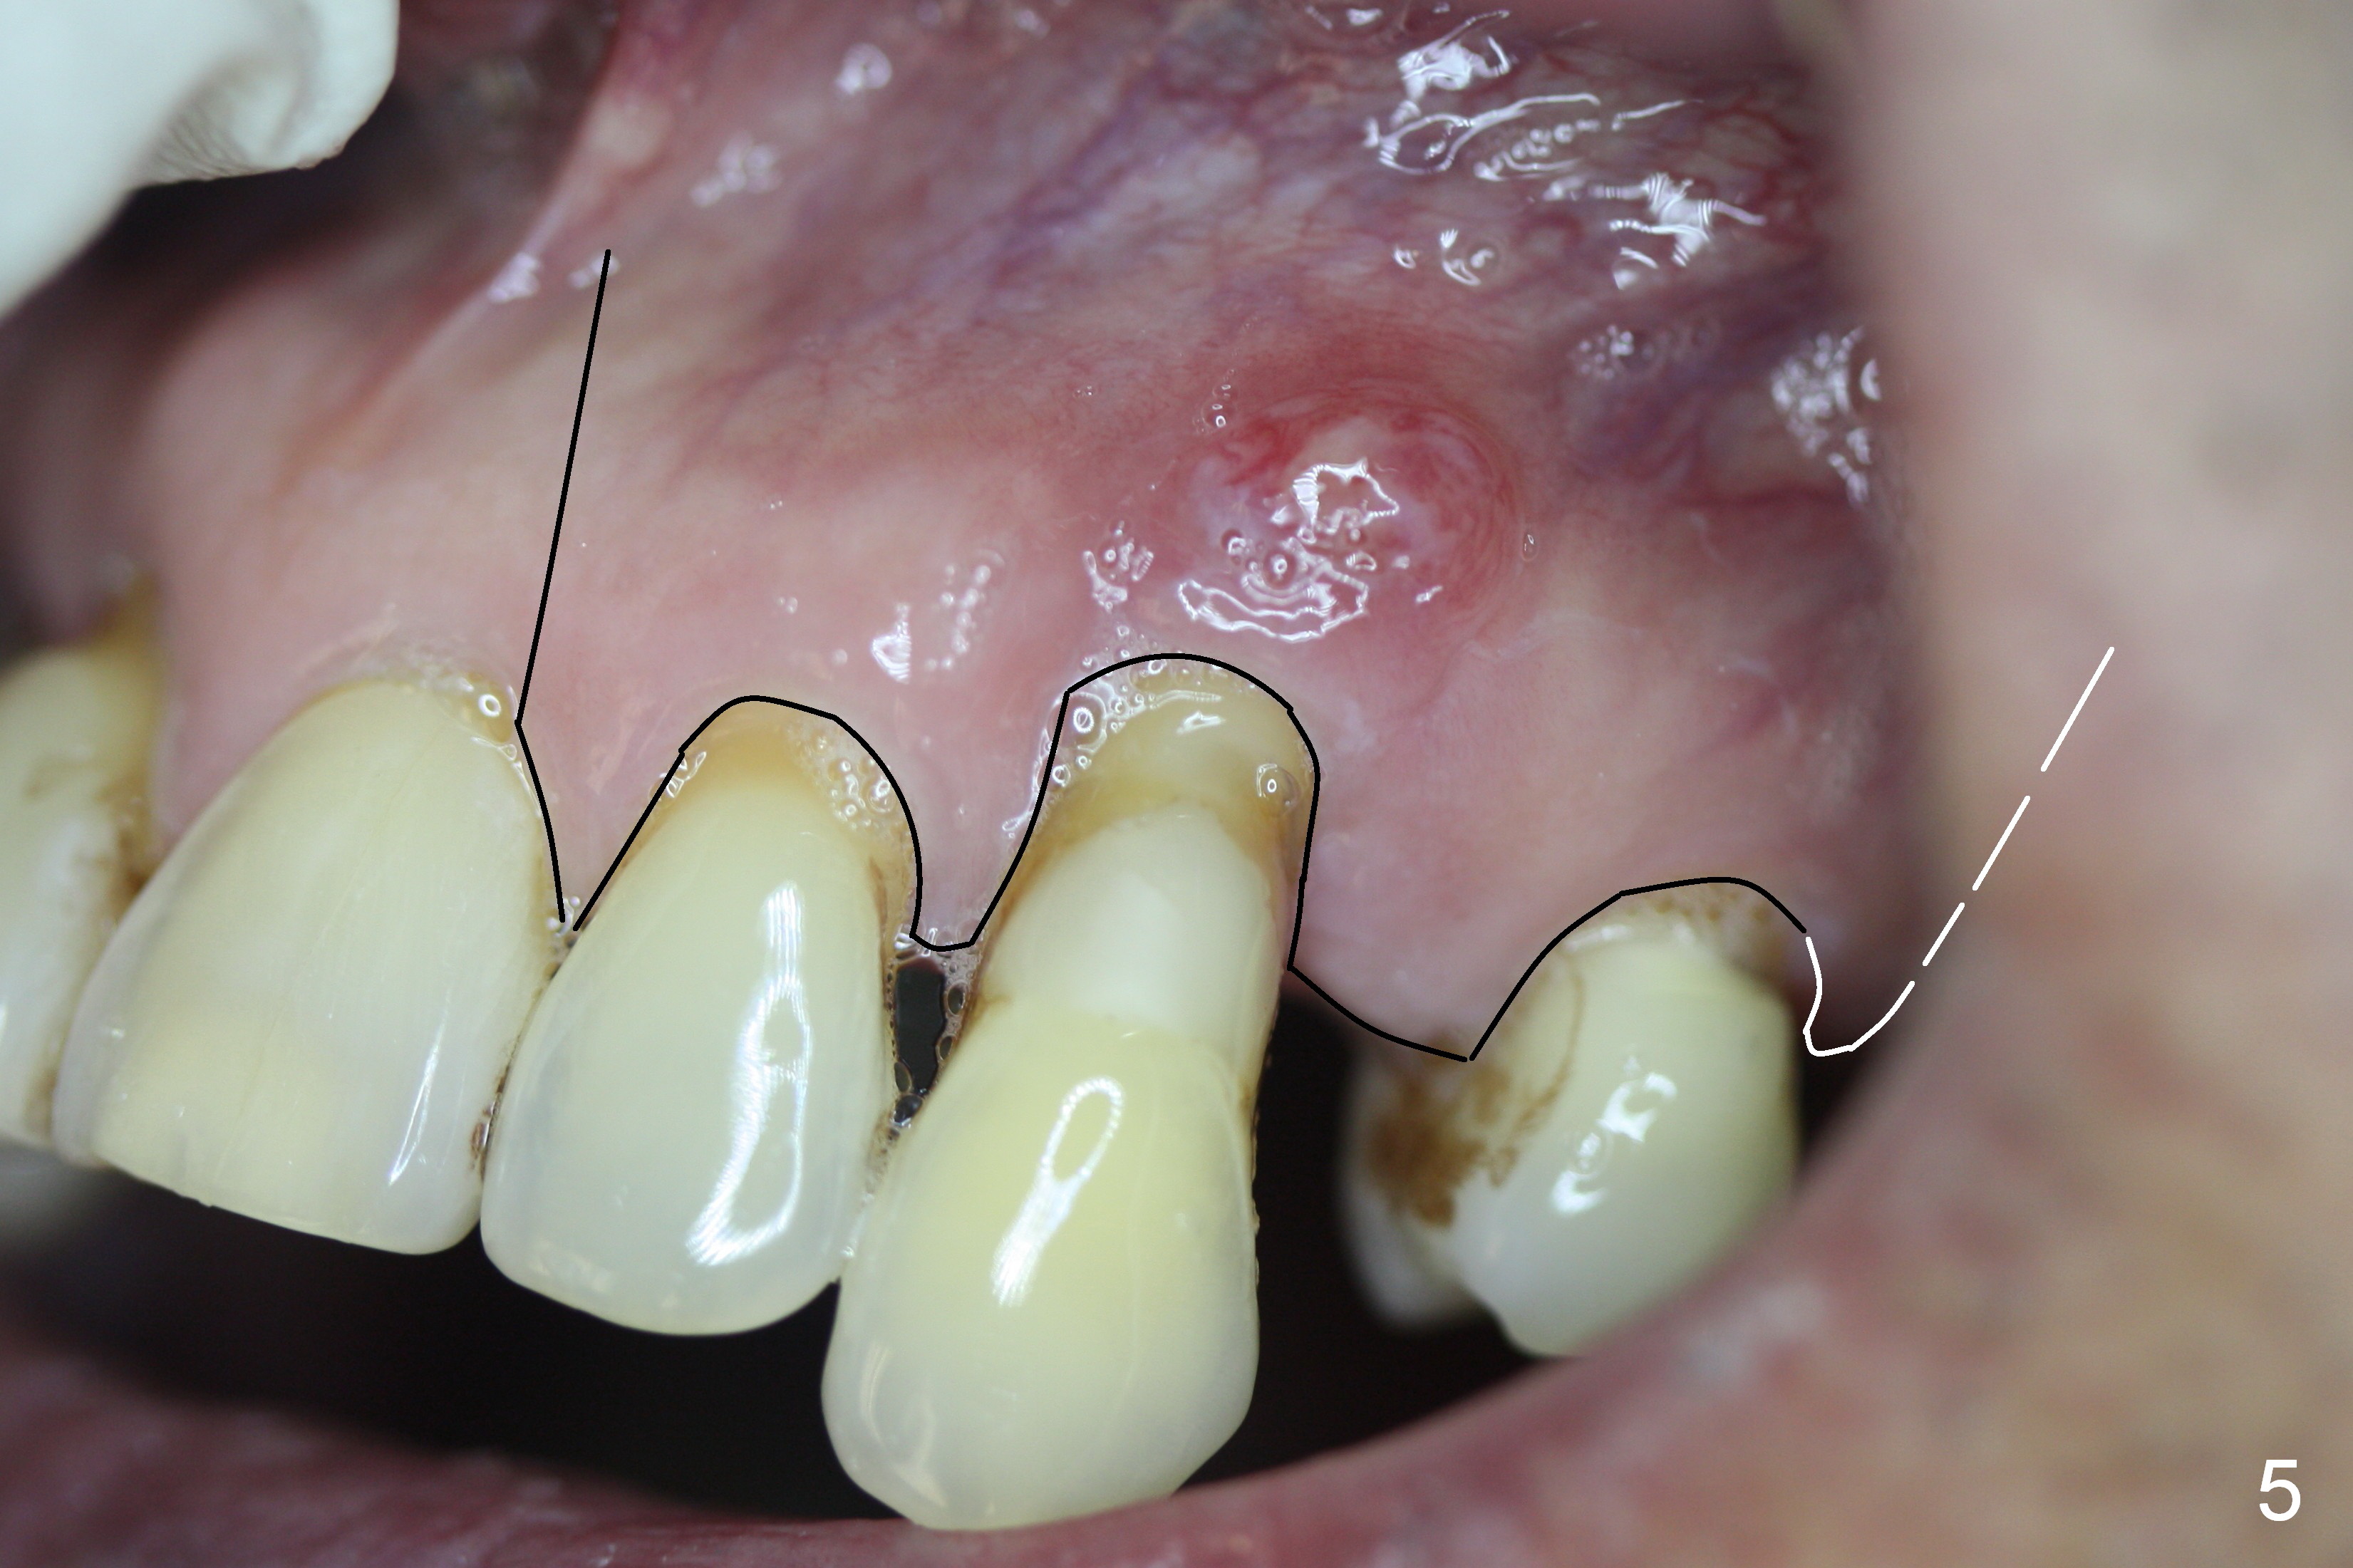

A 65-year-old man has history of Type II diabetes and stroke. He is taking a blood thinner (Xarelto 20 mg qd). The tooth #11 has been mobile for several years. Fig.1 is a CBCT taken 2 years 8 months earlier. The affected tooth has now supraerupted (Fig.2 arrow) with apical abscess (arrowhead).

Bone defect at present should be more severe than CBCT coronal (Fig.3) and axial (Fig.4) sections indicate. After palatal placement of a 5x20 mm tissue level implant (Fig.3 green area) and an appropriate abutment, an immediate provisional is to be fabricated. A block graft is harvested from #12 edentulous region (buccal plate) to the buccal defect at the site of #11 (Fig.4 curved light blue arrow). Prepare surgical handpiece and chisels. The remaining bony defect will be filled with allograft and Osteogen (red circles). The graft site is going to be covered by Osteotape (Fig.3,4 pink curved line), while the donor site is given mixture of allograft and Osteogen and Collagen Dressing. When the soft tissue deficiency is found, connective tissue graft is to be harvested from the palate. If visibility is compromised for these steps, an incision will be made as shown in Fig.5. This should be done with caution considering the medical conditions. Before surgery, ask the patient whether the blood thinner has stopped for a few days or not and how diabetes control is.